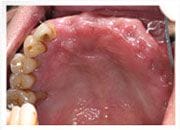

治療前